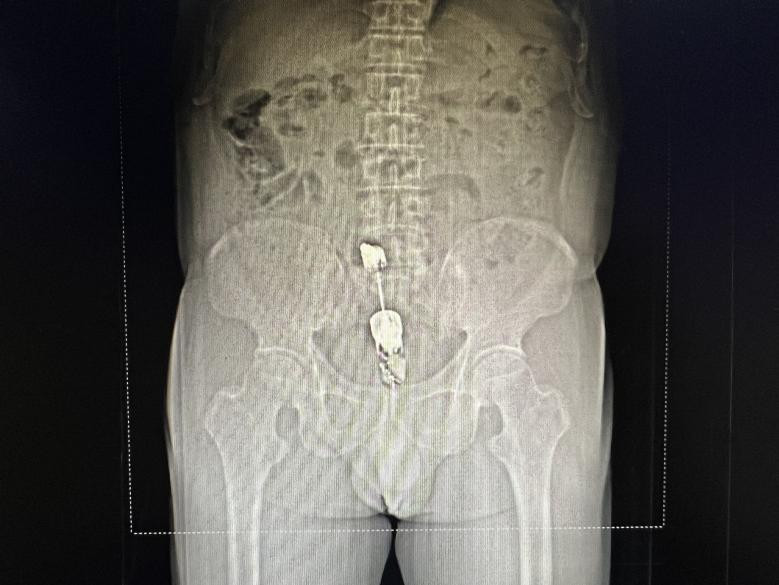

黄播 急诊科医护接到电话后立即出诊,将邹老汉接回院治疗。急诊外科游杰医生立即完善查体,发现棒状物已完全没入邹老汉肛门,又陪同其行腹部CT检查后发现其尾部距离肛缘5cm。邹老汉下腹坠胀难忍,大汗淋漓,十分担心异物难以取出。为尽快取出异物,游杰医生联系肛肠科谢亚朦医生进行急诊手术。终于在当日凌晨手术成功取出了邹老汉的体内异物,手术顺利,安返病房。邹老汉于术后两天,未发现并发症,已平安出院。

CT发现体内异物